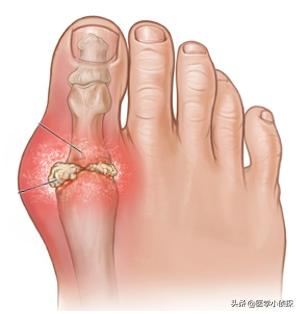

関節の周囲や耳介に痛風結節があり、長期にわたる痛風の場合、関節は萎縮し、変形し、しばしば潰瘍化し、傷口からカルキ状の分泌物が出る。

痛風結石はほとんどすべての痛風患者の体に見られ、病気が進行するにつれて蓄積していく。は手足の関節を破壊し、慢性的な関節の腫れや痛み、こわばりや変形、さらには骨折を引き起こす。

痛風発作が繰り返されると、痛風は悪化し、慢性的に進行し、関節の変形を引き起こします。最終的には、関節や腱の周囲に尿酸塩結晶が沈着し続けることによるダメージのため、関節の動きが徐々に制限されていきます。

痛風結石の発見

皮下の痛風結石の典型的な部位は耳介で、反回関節周囲、タカサゴ、アキレス腱、膝蓋囊などが一般的である。外観は皮下に大小さまざまな黄白色の赤色を帯びた菌が隆起し、皮膚表面は薄く、破れると白い粉状またはペースト状のものが排出され、長期にわたって治癒しない。皮下痛風結石はしばしば慢性痛風結石性関節炎と併発する。痛風結石が関節に大量に沈着すると、関節骨の破壊、関節周囲組織の線維化、二次的な退行性変化を起こすことがある。

尿酸結晶が沈着しやすい部位には、痛風結節と呼ばれる結節状の硬い尿酸結晶の塊ができ、しばしば痛風結石と呼ばれる。痛風結石は関節だけでなく、耳たぶなど体温の低い部位にもできることがあります。

さらに、尿酸塩結晶は軟骨、滑膜、腱、軟部組織、その他の局所的な皮下組織沈着物にも沈着し、数mmから数cmの大きさの痛風結石が形成される。この時、痛風は散発性の単関節炎から再発性の多関節炎、さらには持続性の関節炎、関節変形、尿酸塩結晶へと進行する可能性がある。痛風結石は関節や関節腱に直接影響を与えるため、関節の動きに大きな制限をもたらし、関節の痛みだけでなく、骨の損傷や機能障害を引き起こすこともあります。